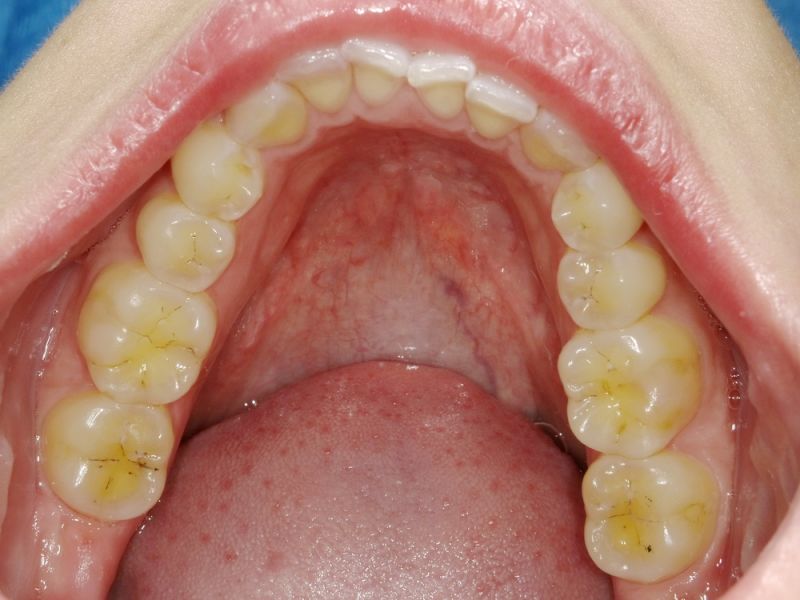

Ganz aktuell war die Patientin bei einer Hauszahnärztin, die auf die Idee kam der Patientin zwei Eckzahnfacetten im Oberkiefer zu installieren, mit dem Ergebnis, dass die Beschwerden der Patienti sich nochmals verschlechtert haben.

Es erfolgen die Maßnahmen der funktionellen Erstuntersuchung und die Herstellung und Eingliederung eines adjustierten Aufbissbehelfs zum Nachweis einer CMD.

Es erfolgen die Maßnahmen der klinisch manuellen Erstuntersuchung und nachfolgend die Maßnahmen zu Herstellung und Eingliederung eines adjustierten Aufbissbehelfs